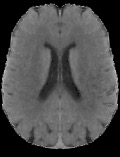

Accurate infarct segmentation in non-contrast CT (NCCT) images is a crucial step toward computer-aided acute ischemic stroke (AIS) assessment. In clinical practice, bilateral symmetric comparison of brain hemispheres is usually used to locate pathological abnormalities. Recent research has explored asymmetries to assist with AIS segmentation. However, most previous symmetry-based work mixed different types of asymmetries when evaluating their contribution to AIS. In this paper, we propose a novel Asymmetry Disentanglement Network (ADN) to automatically separate pathological asymmetries and intrinsic anatomical asymmetries in NCCTs for more effective and interpretable AIS segmentation. ADN first performs asymmetry disentanglement based on input NCCTs, which produces different types of 3D asymmetry maps. Then a synthetic, intrinsic-asymmetry-compensated and pathology-asymmetry-salient NCCT volume is generated and later used as input to a segmentation network. The training of ADN incorporates domain knowledge and adopts a tissue-type aware regularization loss function to encourage clinically-meaningful pathological asymmetry extraction. Coupled with an unsupervised 3D transformation network, ADN achieves state-of-the-art AIS segmentation performance on a public NCCT dataset. In addition to the superior performance, we believe the learned clinically-interpretable asymmetry maps can also provide insights towards a better understanding of AIS assessment. Our code is available at https://github.com/nihaomiao/MICCAI22_ADN.